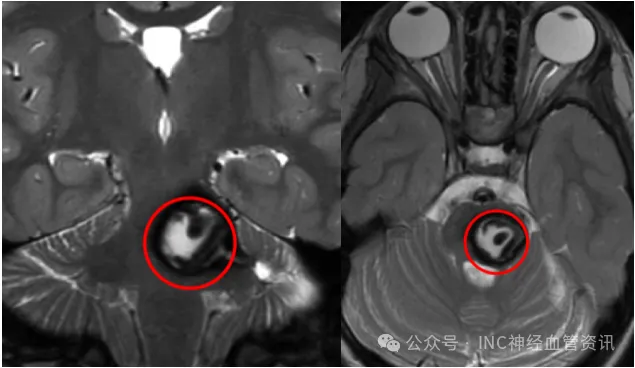

平时无任何症状的20岁女孩,怎么就突发脑干出血,偏瘫昏迷?

一说到脑瘤,绝大多数人的脑海里马上就会浮现出这样的画面:恶心呕吐,头痛不止,视力下降、走路不稳,严重甚至生活不能自理事实真的全然如此吗?当然不是! 这样回答,肯定会有人反...